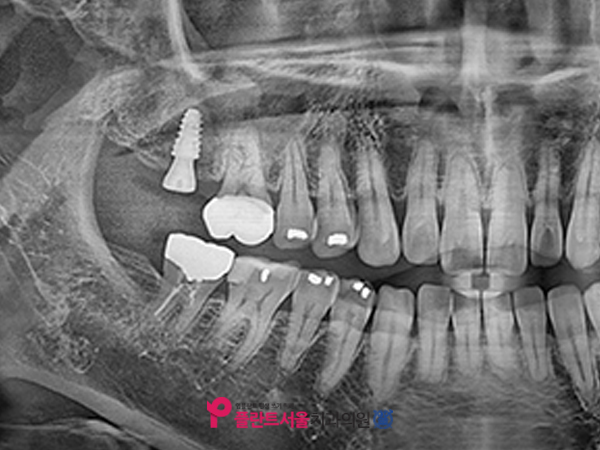

환자에게 축농증 치료를 받고, 다시 저희 병원에 내원하셨을 때 촬영한 CT 사진입니다. 각종 이물질로 되어 있던 부위가 이전에 비해 상당히 완화된 것을 확인할 수 있습니다. 치료 후 사진을 보면, 상악동 아래 쪽에 이물질이 남아 있습니다만. 이는 수술 직후 일시적으로 자극받은 점막이 부어오르는 현상으로 식립을 진행해도 문제가 없다고 판단해 임플란트 시술을 하게 되었습니다.

좌-X-ray 사진 / 후-CT 사진

뼈 이식을 실시한 후에는 뼛속에 픽스처를 안전하게 심은 모습입니다. 올바른 위치와 방향으로 깔끔하게 심어졌고, 상악동 안을 채웠던 이물질도 많이 개선되었습니다.